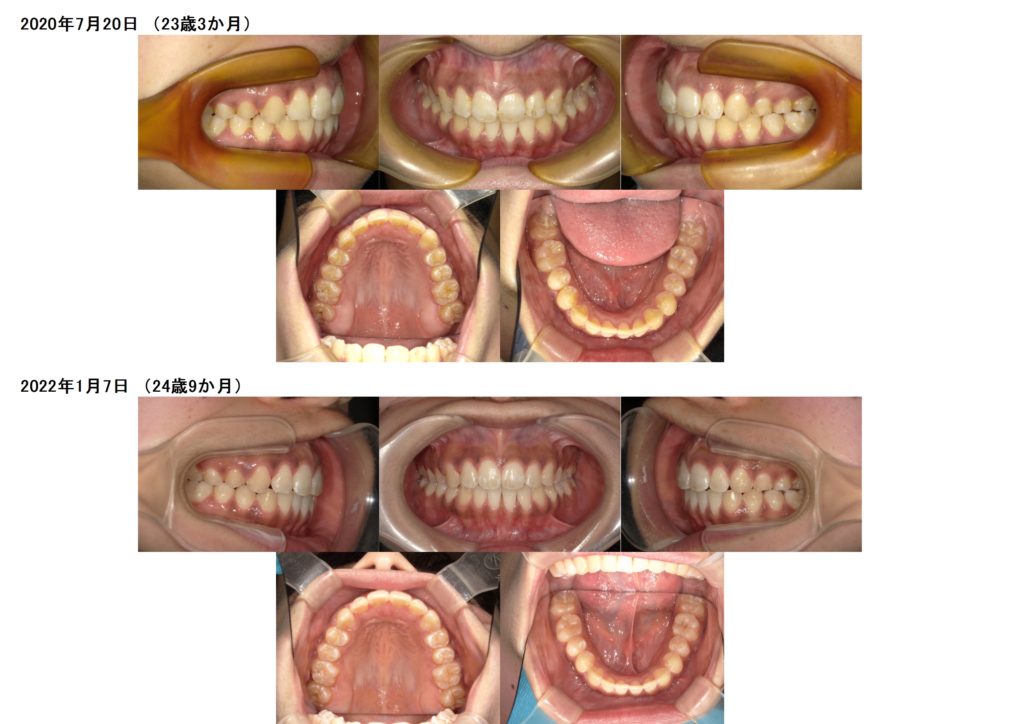

上下の写真を見比べてみると上下の顎の土台をしっかりと整ったのが分かると思います。

特に、上のアーチの形が変わったのが分かりますよね☆

ここから、リテーナーと呼ばれる保定装置を使用して頂くのですが、リテーナーでも、少しの動きをする事が可能なので、微調整をしながら、しっかりと保定をしていきます☆

しっかりとリテーナーを使用して、保定もキレイにできています☺

このように、少しずつの変化ですが、マウスピースでもどんな歯並びの方でも可能です。

しっかりと噛み合わせを重視し、奥歯から全体の歯をしっかり動かし、歯並びを並べていくと、後戻りのリスクも減らせますし、土台の変化をする事が出来るのでお口の中もとてもきれいに整います。